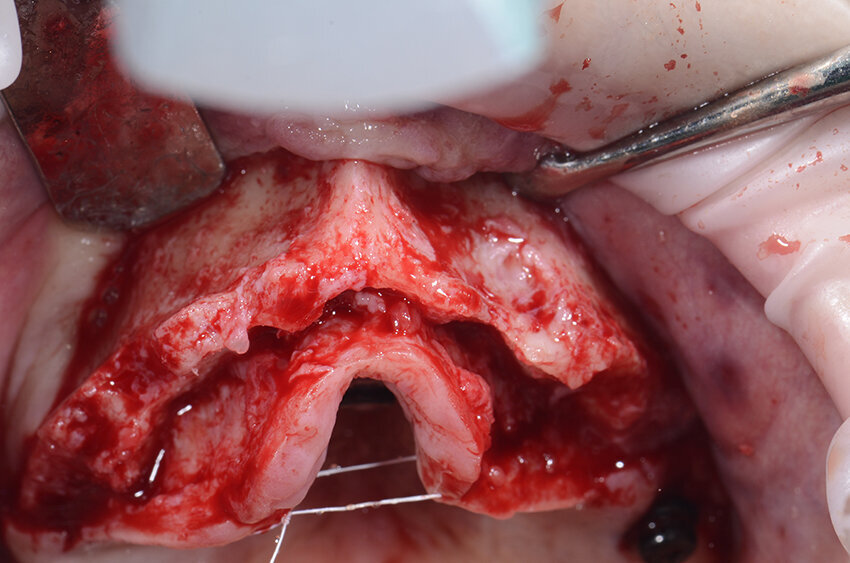

Quello che troviamo è un’atrofia marcata in senso orizzontale nella zona della pre-maxilla che si estende anche nei settori latero-posteriori. Terminata la parte più importante dell’intervento ci dedichiamo a verificare il fit della griglia customizzata. È sorprendente ogni volta constatare l’alta affidabilità del posizionamento tridimensionale (Fig. 10). Il riempimento della griglia viene effettuato con osso autologo raccolto con Safe Scraper e con pinze ossivore che ci consentono anche di regolarizzare la cresta nella zona di intervento, miscelato al 50% con osso Bovino Deproteinizzato (Geistlich Bio-Oss, Geistlich Pharma).

In casi come questo, consiglio di non riempire completamente la griglia con l’innesto per evitare difficoltà nel posizionamento; prima di posizionare la griglia si colmano eventuali lacune nel riempimento con biomateriale (Geistlich Bio-Oss, Geistlich Pharma AG, Wolhusen, Switzerland). Dopo aver posizionato la griglia si utilizzano quattro viti, due vestibolari e due palatali, per renderla totalmente stabile (Figg. 11, 12). La griglia viene quindi ricoperta con una membrana in collagene riassorbibile Geistlich Bio-Gide (Geistlich Pharma AG) per migliorare la guarigione dei tessuti e per prevenire la migrazione del tessuto molle all’interno dell’innesto (Fig. 13).